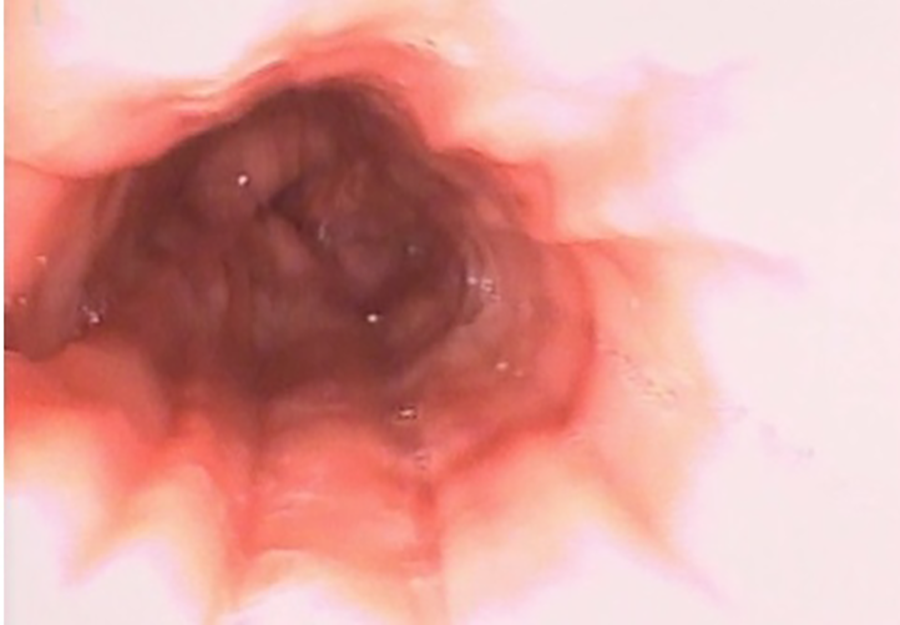

Esophagus-gastro-duodenoscopy (EGD) revealed a pale, mild trachealized esophagus with longitudinal furrows (Figure 1), normal gastric mucosa, and the presence of an edematous duodenal bulb associated with a tight stenosis of the descending duodenum (Figure 2); a neonatal endoscope was effective in overcoming the narrowing, and a post-stenotic juxta papillary ulceration was identified (Figure 3). Ileocolonoscopy was normal.

Figure 1. EGD documenting esophagitis in the 3rd esophageal tract characterized by reduced wall distensibility, trachealization and furrows.